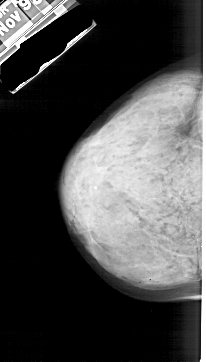

A_1874_1.LEFT_CC

LEFT_CC LINES 5056 PIXELS_PER_LINE 2881 BITS_PER_PIXEL 12 RESOLUTION 43.5 NON_OVERLAY